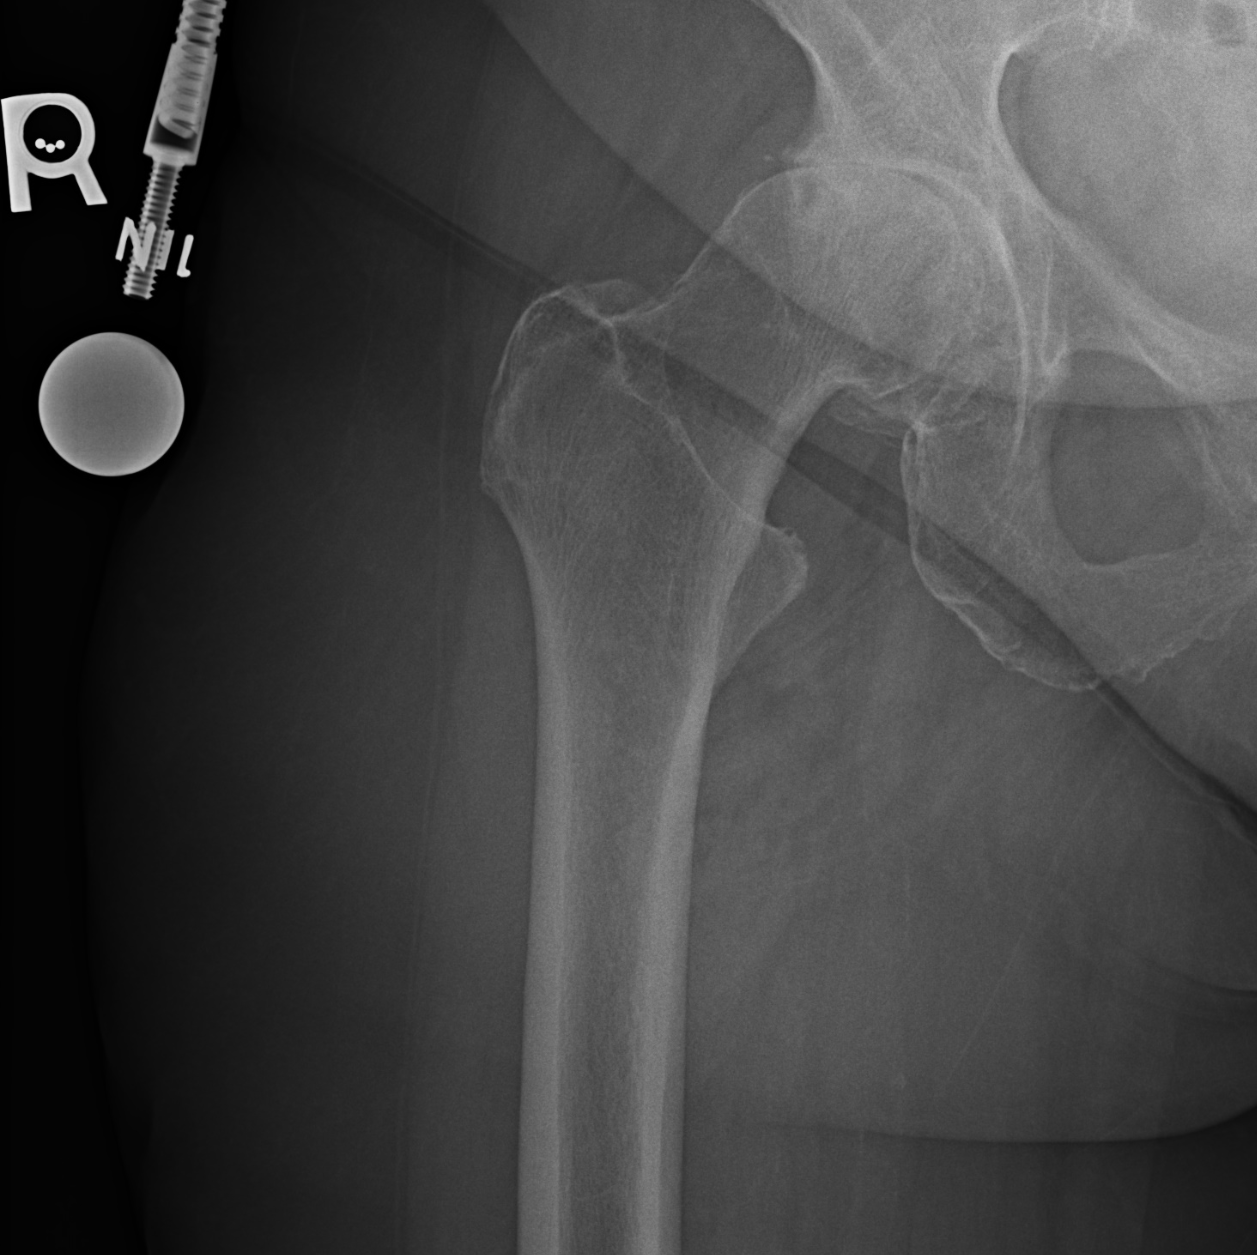

The x-ray performed during her visit Dr. Denehy demonstrated a shrinking joint space, indicative of end-stage arthritis of her right hip. A picture of her pre- and post-op x-ray is below: